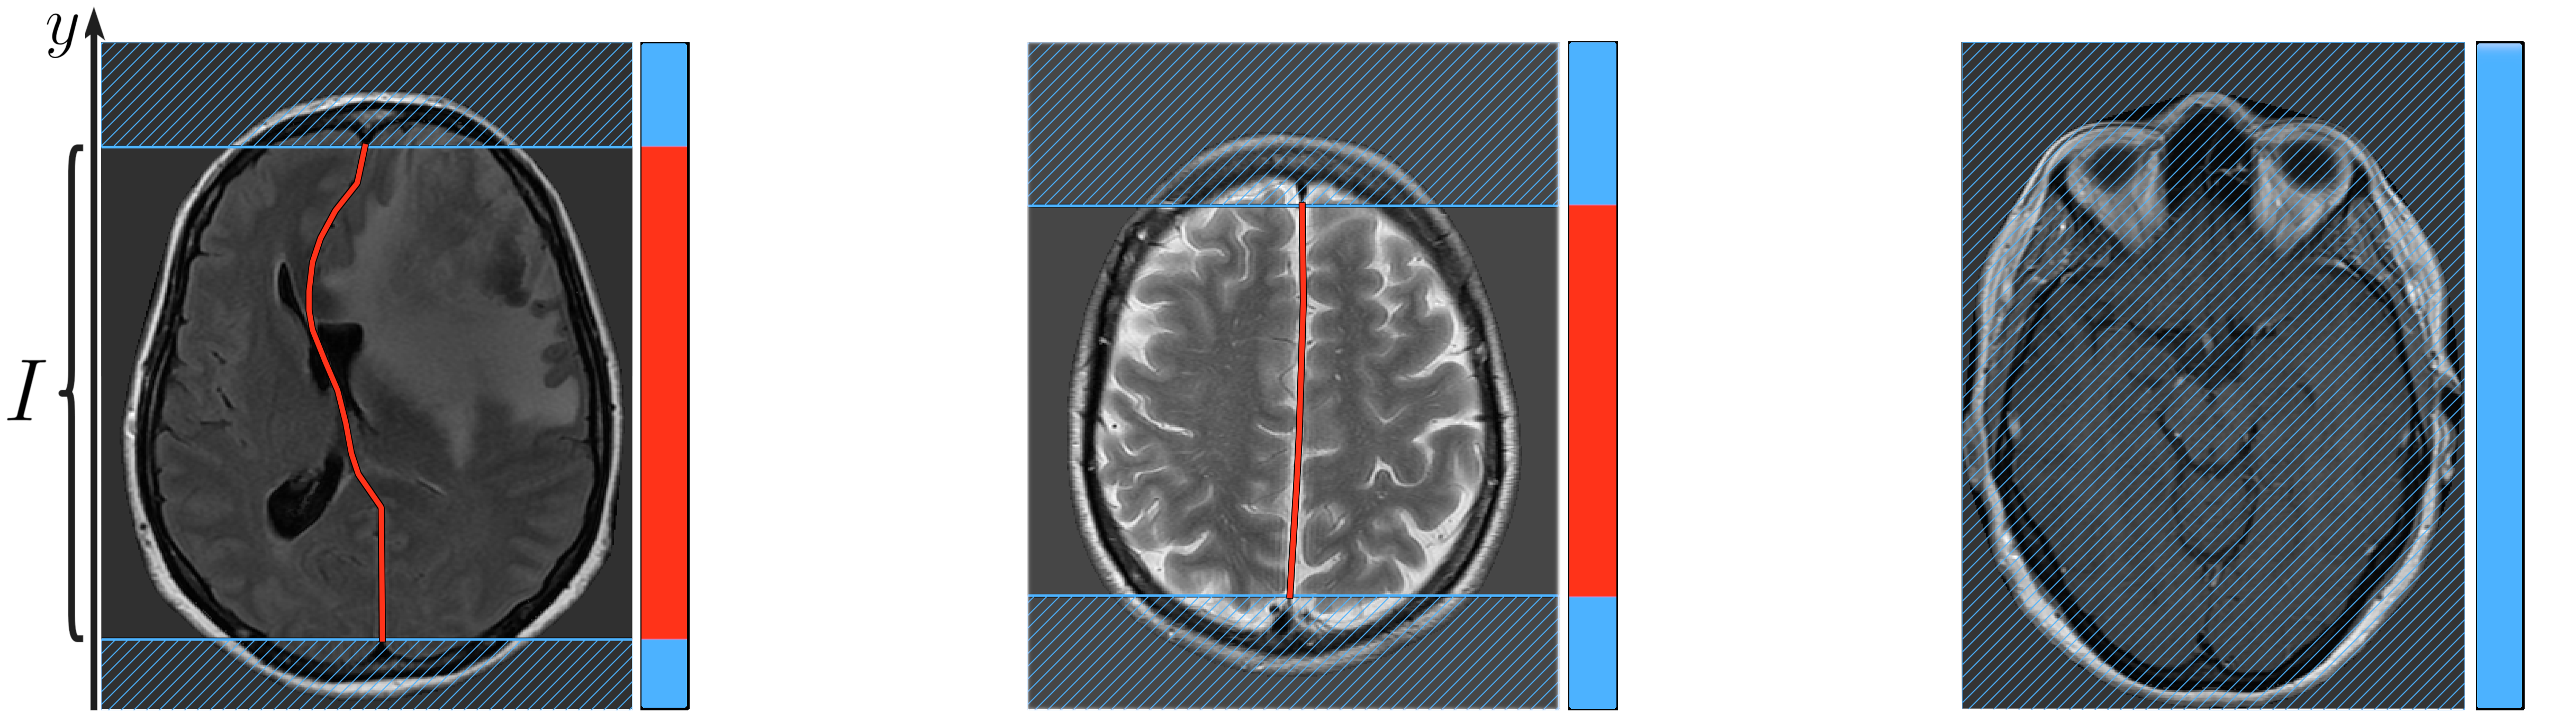

Refer to caption

Figure 2: The binary masks of the regions where the midline is defined (red). Note the rightmost image, for which the midline is undefined everywhere.

The key structural facts are: 1) for each coordinate y𝑦y there is at most one x𝑥x-coordinate, which is refered as midlineysubscriptmidline𝑦\textbf{midline}_{y}, such that the pixel (midliney,y)subscriptmidline𝑦𝑦(\textbf{midline}_{y},y) is situated on the midline; 2) midlineysubscriptmidline𝑦\textbf{midline}_{y} exists only for y-coordinates within certain interval I𝐼I on the Oy𝑂𝑦Oy axis to which binary mask we refer as limits (Fig. 2).

4.2 Limits prediction

Since the proposed midline estimation approach yields midlineypredsuperscriptsubscriptmidline𝑦pred\textbf{midline}_{y}^{\text{pred}} for all y𝑦y-coordinates, we need to filter out the predicted values for the regions where the midline is not defined (Fig. 2, hatched). The corresponding limits are obtained by thresholding the second head’s output (limitspredsuperscriptlimitspred\textbf{limits}^{\text{pred}}) and taking the convex hull.